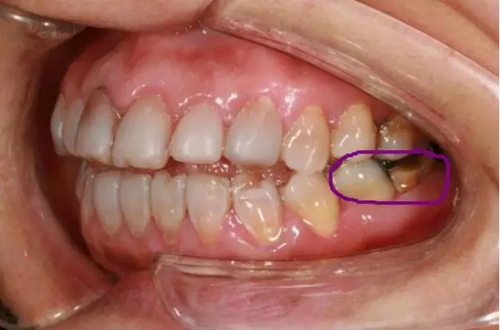

5,粉色線牙齒缺損(圖二)

美學修復(fù)不單是指擋擋門面,同時我們應(yīng)恢復(fù)患者正常的生理頜位及咬合關(guān)系,在滿足美觀的同時恢復(fù)患者的咀嚼功能。

(圖二)